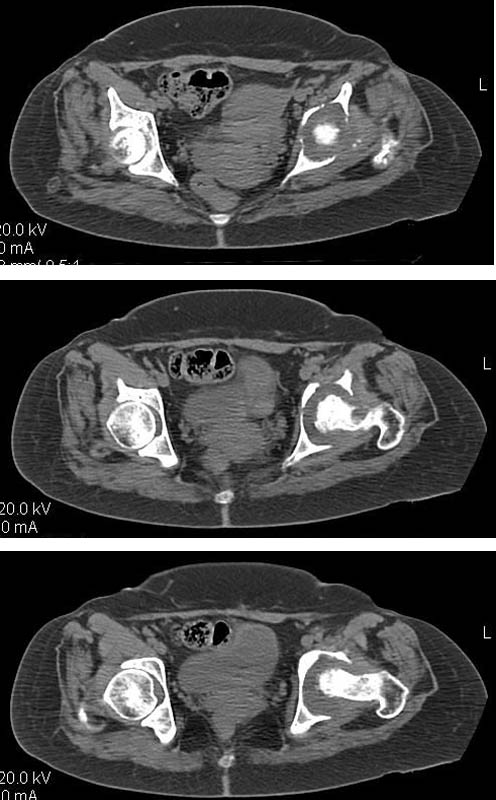

Женщина, 45 лет. В марте перенесла левосторонний коксит неизвестной этиологии. Специфику и онкологию исключили.

Интраартикулярных инъекций не было. Сейчас процесс клинически и рентгенологически - стабилизировался. Состояние вполне удовлетворительное.Предполагается тотальное эндопротезирование с пластикой полости аутокостью. Возможна ли бесцементная <чашка>? Заранее благодарю! С уважением,А.В.Владзимирский

Дополнение - проконсультировался с женой-она специалист рентгенолог - на КТ большое колиество мягкотканного компонента - ищите микоплазмы или бруцеллу. Я склоняюсь к виопсии.

Пртезирование через пол года после коксита закончившегося лизисом сустава, который на снимках выглядит как гнойный? Что значит неизвестной этиологии?

Уважаемый коллега! Последняя версия - мы пролистали ренгенологическую книженцию-так картинка вполне подходит под сустав Шарко (neuropatic joint ). В тазобедренном суставе патология редкая (но меткая). Ищите причину - варианты - нейросифилис, сирингомиелия, опухи спинного мозга (и выше тоже) компрессия спинного

мозга извне, рассеяный склероз, алкоголизм. А так-же : склеродерма ,Рейно,ревматоидный артрит, амилоидная инфильтрация нервов,и это не считая всяких менингеомиелоцеле,asymbolia,Riley-Day syndrom,и все возможные другие нейропатии. На данном этапе не спешите оперировать(протезирование протиопоказано при нейропатических суставах),проконсультируйтесь с классным невропатологом,сделайте МЯР головного озга и

весь позвоночник. И держите нас в курсе - случай крайне интересный :)